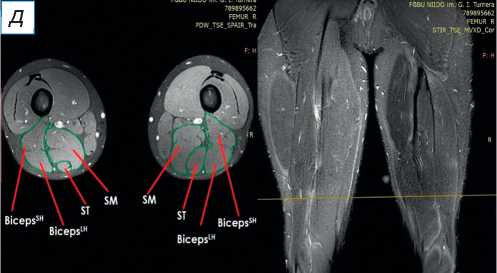

При поступлении в центр пациенту выполнены лучевые методы исследования нижних конечностей, в частности панорамная рентгенография и компьютерная томография (КТ) нижних конечностей; сравнительная МРТ мягких тканей правого и левого бедра (рис. 2). По данным рентгенографии и КТ-исследования, костно-суставной патологии не обнаружено. По результатам МРТ определены повреждения всех трёх мышц различной степени тяжести — SM, ST, BicepsLH (расположены в порядке убывания; см. рис. 2, а ). Длинная головка двуглавой и полусухожильная мышцы, вероятно, были оторваны у места крепления и не подверглись значительной ретракции; начало брюшка полуперепон-чатой мышцы визуализировано на границе верхней и средней трети бедра (ретракция 9 см).

Рис. 2. Сравнительная магнитно-резонансная томография мягких тканей правого и левого бедра (аксиальные и фронтальные срезы): а — изменение нормальной архитектоники полусухожильной, полуперепончатой и длинной головки двуглавой мышцы на уровне верхней трети правого бедра; б — на данном уровне не прослеживается мышечное брюшко полуперепончатой мышцы; в — на границе верхней и средней трети прослеживается мышечное брюшко полуперепончатой мышцы, спаянное с большой приводящей; определяется разница по форме и диаметру поперечника полусухожильной мышцы; г — на уровне средней трети отчётливо проявляются мышечное брюшко полусухожильной мышцы, несоответствие поперечного диаметра полуперепончатой и полусухожильной мышц с контралатеральной стороной, гипертрофия короткой и длинной головки бицепса; д — аналогичная картина и на границе средней и нижней трети. ST ( m. semitendinosus ) — полусухожильная мышца; SM ( m. semimembranosus ) — полуперепончатая мышца; BicepsLH ( m. biceps femoris ) — длинная головка двуглавой мышцы.